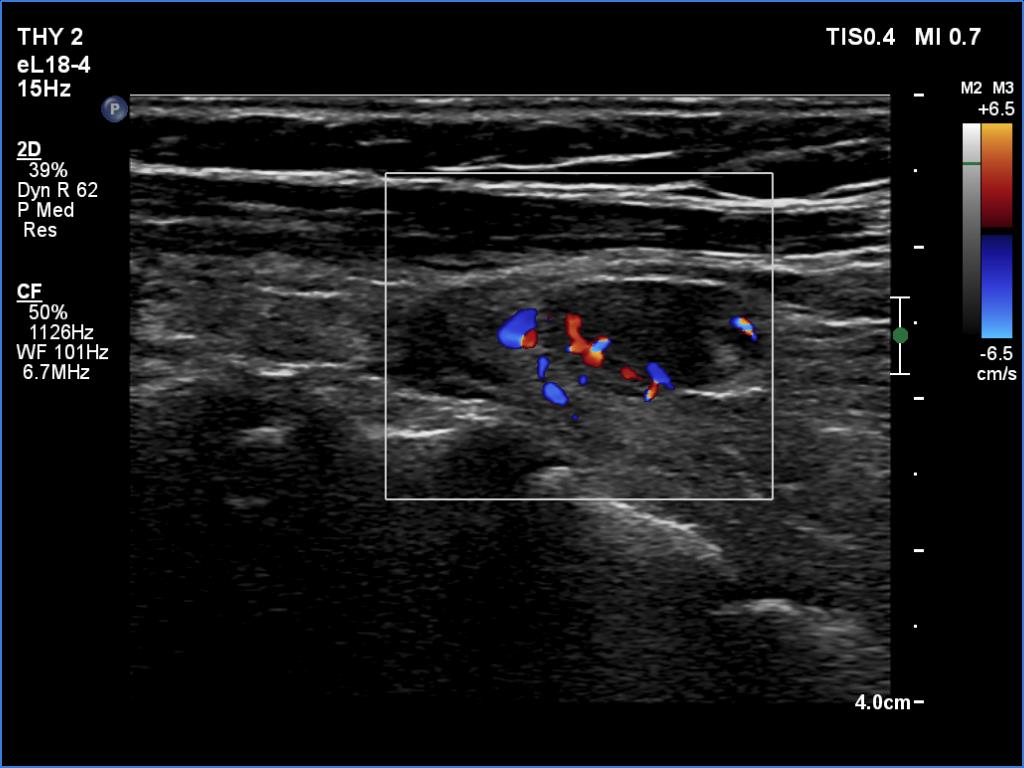

Ultrasonography. The thyroid was atrophic and hypoechoic. There was a hypoechoic mass under the lower pole of the left lobe.

Ultrasound-guided aspiration cytology resulted in benign lesion.

Wash-out parathormone 1101 ng/mL.